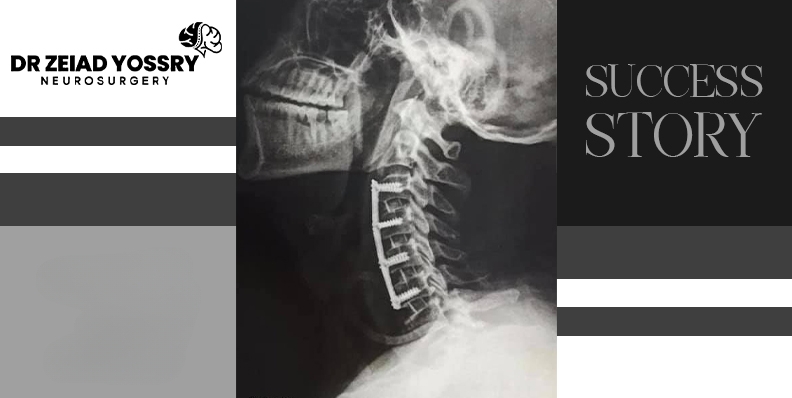

The goal of surgery was to relieve pressure on the spinal cord and nerves, thus restoring function to the limbs. Dr. Zeiad Yossry performed a discectomy and vertebral stabilization through an incision in the neck, where the portion of the disc that was compressing the nerve root was removed. Some vertebrae were then permanently fused using screws and plates, providing support to the cervical vertebrae.